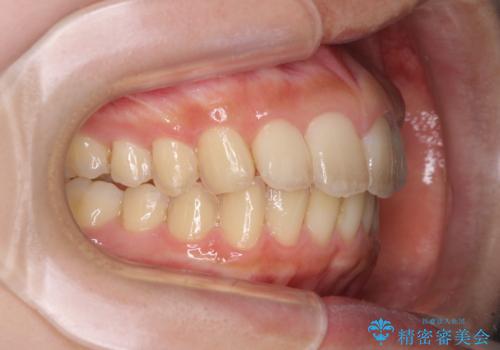

就職前にきれいな歯並びにしたい 大学生のインビザライン矯正

- 就職するまでに歯並びをきれいにしたいとのことで来院された患者様です。

前歯の叢生を気にしていましたが、極力突出感を改善できるようにすることとし、インビザラインにて矯正治療を行うこととしました。

改善の期待できない口元の突出感改善を希望されたため、いたずらに治療期間が延びましたが、きっちりと仕上がりました。